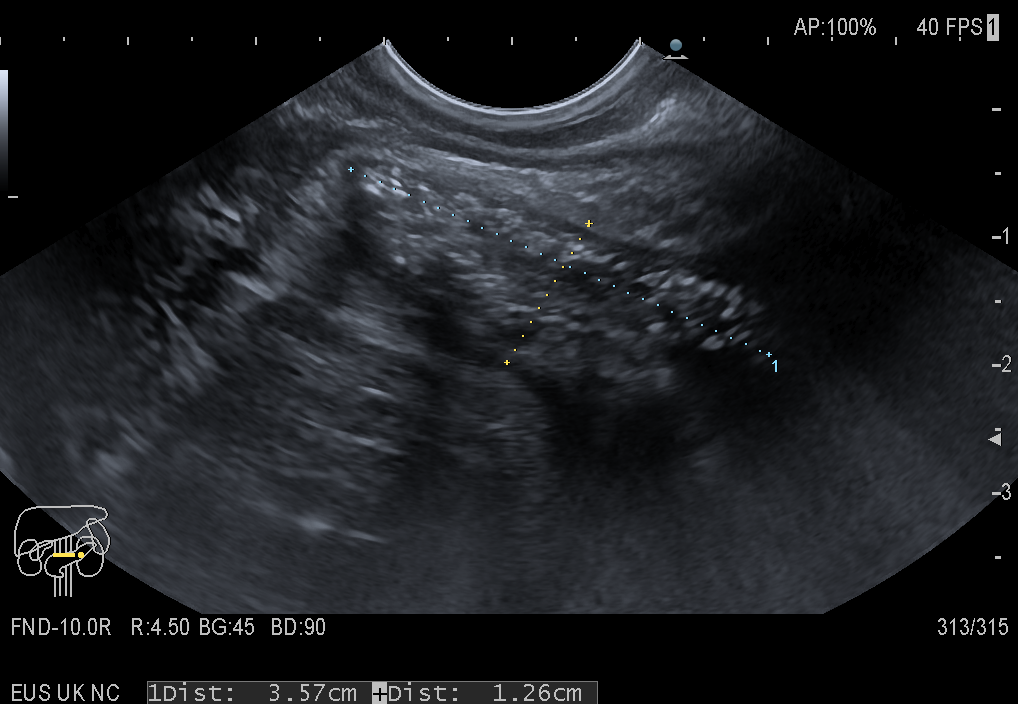

Endorectal ultrasound (ERUS) performed with a linear flexible EUS scope shows a well-defined, circumscribed, collection filled with mixed hypoechoic and hyperechoic content (Image 1 + 2). Intravenous CEUS (4.8 mL) depicted uptake of the ultrasound contrast agent inside various septations and granulation tissue in the collection (Video 1). Transrectal injection of diluted Sonovue (0.2 mL in 10 mL of saline) depicted the extent of the pararectal collection which communicated with a cranial and caudal fistula (Video 2). The EUS-guided aspirate yielded pus, with later growth of Enterobacter + anaerobe species. Last but not least, perineal CEUS examination with a convex probe showed the horseshoe abscess surrounding the rectum (Video 3).